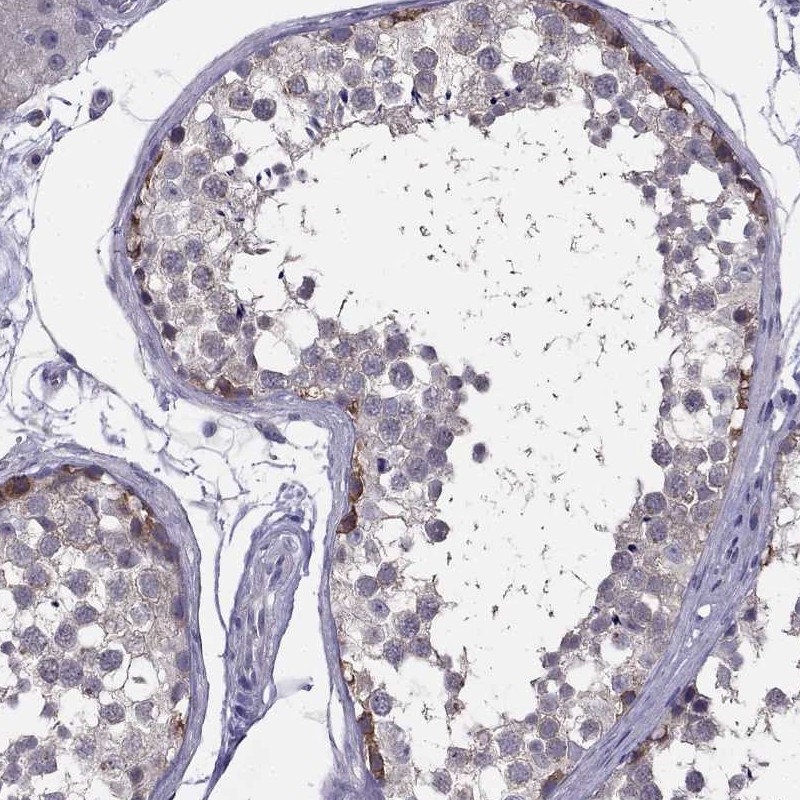

Immunohistochemical staining of human testis shows moderate cytoplasmic positivity in cells in seminiferous ducts.